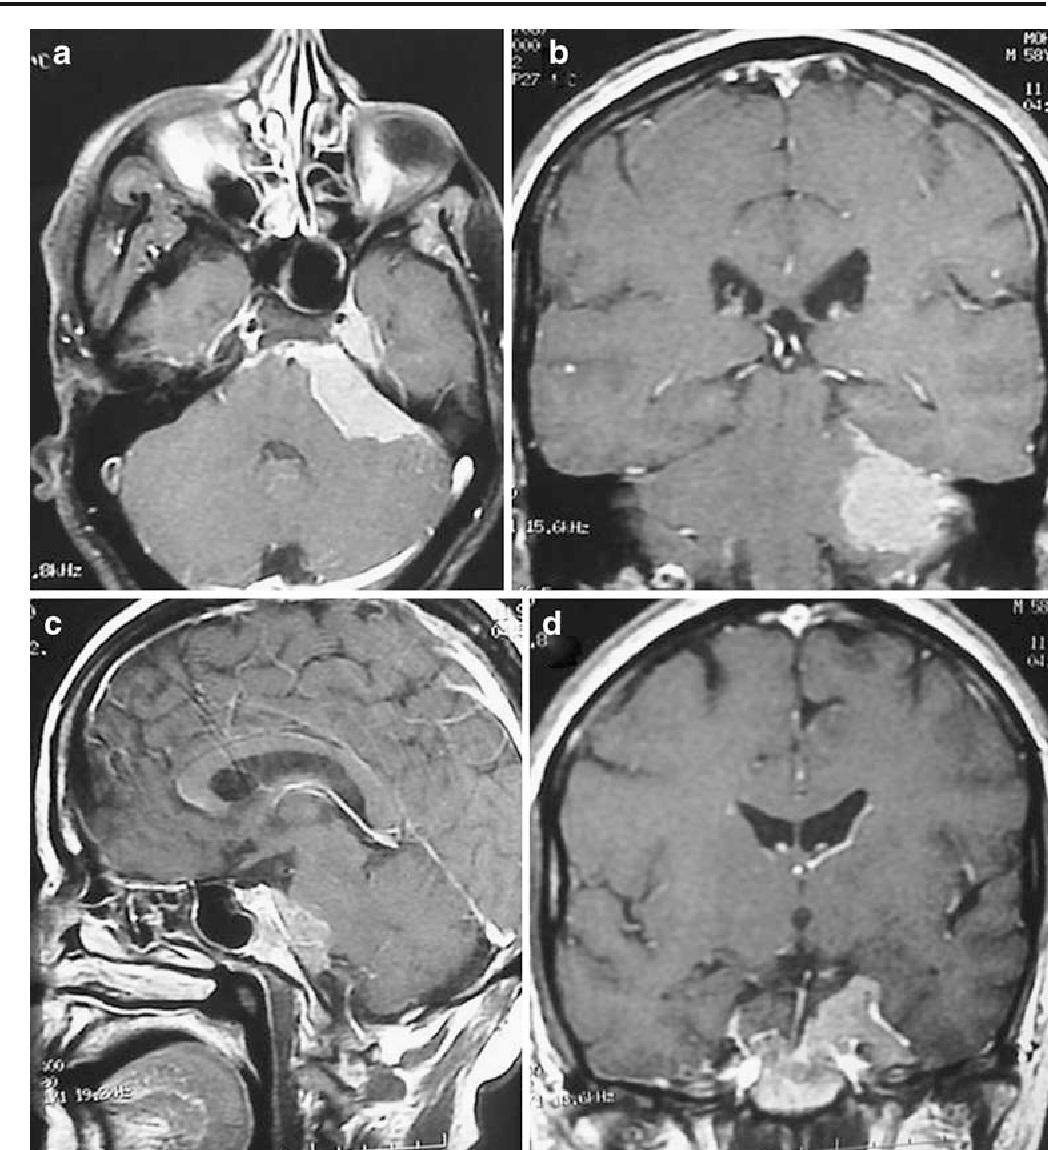

一般而言,磁力共振檢查可以清楚診斷天幕裂孔區是否有腦膜瘤。這個位置位於腦內深處,空間非常狹窄,解剖結構亦十分複雜,附近的靜脈系統包括大腦內靜脈、基底靜脈、大腦大靜脈、小腦前中央靜脈、天幕裂孔區松果體後方深靜脈系統等等。

切除這區域的腦膜瘤,手術一定要採用適合的手段方法,設計手術方案時需要盡量露出腫瘤,以減少對腦組織牽拉及降低對靜脈竇的損傷。神經外科醫生通常會利用顯微鏡協助,採取從頭後經天幕、即切開天幕的入路方式進行,可以充分露出腫瘤,特別適合橫跨天幕的腦膜瘤,有助提高切除率之餘,同時又可減少對周邊組織牽拉的情況。